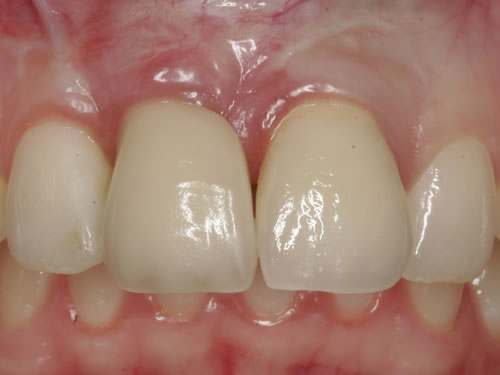

Eine besondere Herausforderung ist die Oberkieferfrontzahnregion. Der Wunsch nach einem perfekten Resultat ist geradezu selbstverständlich. Jeder möchte große, weiße Zähne und ein gesundes, reizloses Zahnfleisch besitzen (Abb. 3.30).

Abb. 3.30: Perfektes Resultat einer Versorgung.

Häufig führt ein Zahnverlust zu einem Verlust von Knochen (Hartgewebe) und der bedeckenden Schleimhaut (Weichgewebe). Besonders im sichtbaren ästhetisch sensiblen Bereich ist es aber notwendig, dass sowohl Hart- als auch Weichgewebe so wiederhergestellt wird, dass im Idealfall das Zahnimplantat mit seiner Krone dem Aussehen des ehemaligen gesunden Zahn entspricht. Als Erfolgskriterien werden aus zahntechnischer Sicht die Form, Farbe und Größe der individuellen Krone angesehen. Aus medizinischer Sicht gibt es wichtige Erfolgskriterien, die die Implantatposition, die Implantatlänge, den Implantatdurchmesser, den Zahnfleischrand im Vergleich zum Nachbarzahn und die Zahnfleischpapillen zwischen den Zähnen beinhalten. Zusätzlich braucht man ein zahntechnisches Labor, das mit der Keramikverarbeitung ein natürliches Aussehen gestalten kann. Nur, wenn alle Parameter perfekt sind, ist das Ergebnis perfekt. Das macht den Einzelzahnersatz im Oberkieferfrontzahngebiet zu einer echten Herausforderung.

Nach der Entfernung von Zähnen kommt es schnell zu Knochenverlust (Resorptionen) und entsprechendem Verlust von Schleimhaut. Die Schleimhaut kann durch bestimmte Operationstechniken wiederhergestellt werden, in dem man freie oder gestielte Bindegewebstransplantate z. B. vom Gaumen entnimmt und das fehlende Material so ersetzt. Das Weichgewebe kann in unterschiedlichen Behandlungsphasen korrigiert werden. In vielen Fällen wird es während der Implantation oder bei der Freilegung verbessert. Manchmal müssen Feinkorrekturen auch nach Eingliederung der fertig gestellten Krone erfolgen, wenn ästhetische Einbußen vorliegen. Häufig hat die Zahnfleischkorrektur auch noch einmal die Änderung der endgültigen Krone zur Folge (Abb. 7.14, 7.15).

Abb. 7.14: Unbefriedigendes ästhetisches Ergebnis nach Implantatversorgung.

Abb. 7.15: Perfektes Ergebnis nach Weichgewebskorrektur und nach Eingliederung der geänderten Krone.